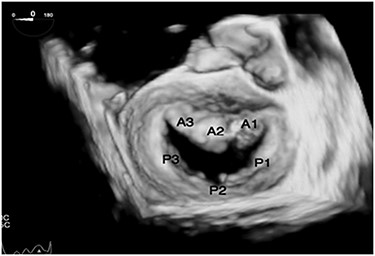

TEE views in a patient with dextrocardia with SI are different than the standard views. In the midesophageal four-chamber view at 0°, the right atrium and the right ventricle are on the right side of the display (Fig. 2A). The midesophageal two-chamber view, usually obtained at a multiplane angle of 90°, is identical to the view seen in a patient with situs solitus (Fig. 2B). The midesophageal aortic valve long-axis view (LAX) was obtained at a multiplane angle of 30–40° (Fig. 2C), while the midesophageal aortic valve short-axis view (SAX) was obtained at a multiplane angle of 120–130° (Fig. 2D). The midesophageal Bicaval view was obtained at 76° (Fig. 2E). The transgastric mid-papillary SAX was obtained as expected at 0° but with the right ventricle on the right side of the display (Fig. 2F). So in summary, TEE views in dextrocardia patients are similar to situs solitus patients at a multiplane angle of 90°, they are mirror images of each other at 0°, while the aortic valve SAX and LAXs are “flipped” in comparison with situs solitus patients. The approach to mitral valve assessment with TEE must be altered [10]. Firstly, the multiplane angles required to assess different parts of the mitral valve leaflets are different. Secondly, when examining the valve using 2D TEE in the midesophageal aortic valve with LAX view in a dextrocardia patient, a leftward rotation of the TEE probe will examine the posterior portion of the valve (A3/P3) while in a situs solitus patient, such a leftward rotation would result in the anterior parts of the valve to be examined (A1/P1). This point is important when discussing mitral valve repairs or the position of paravalvular leaks. If the surgeon stands on the left side of the patient, then the surgical view of the mitral valve will be as shown in Fig. 3.

Transesophageal echo 3D view of mitral valve in dextrocardia as viewed intraoperatively by the surgeon standing on the left side of the patient.